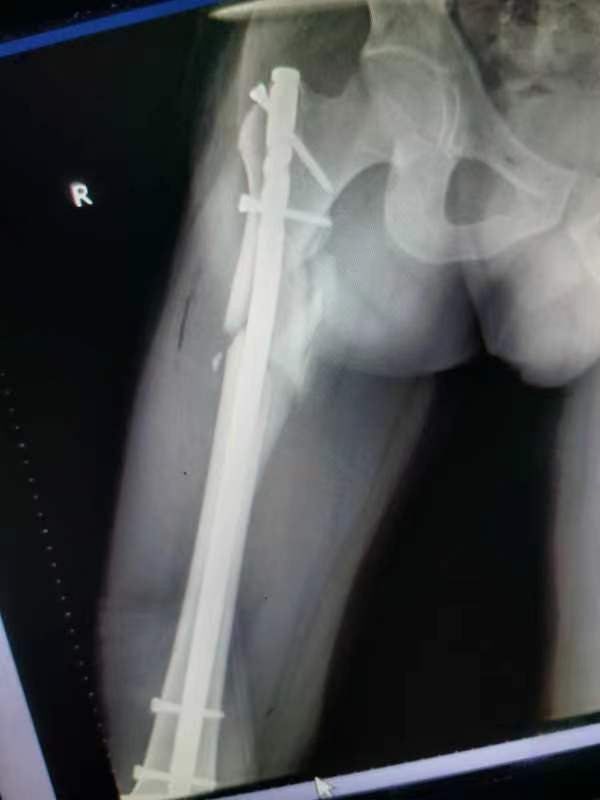

中股网 外伤导致的股骨上段骨折闭合复位股骨重建钉固定,期待早期愈合